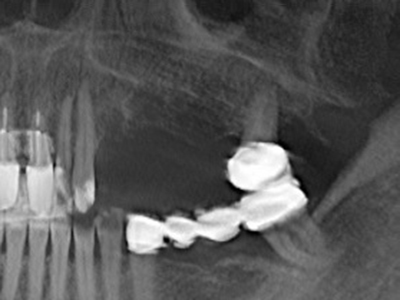

Piezo surgery has additional advantages when harvesting bone blocks. In addition to the high precision with osteotomy described above, the use of the thin saw tips specifically minimizes loss of material. Greater loss of material during harvesting can be expected with the thicker instrument tips, particularly when using Lindemann drills (Lakshmiganthan, Gokulanathan et al. 2012). The basal separation, which is necessary particularly for retromolar block transplants, is simplified by specially designed rectangular saws, with the result that piezo surgery is viewed as a precise, simple and safe procedure for harvesting retromolar bone blocks (Happe 2007) (Fig. 1-12).

Indication: Bone splitting